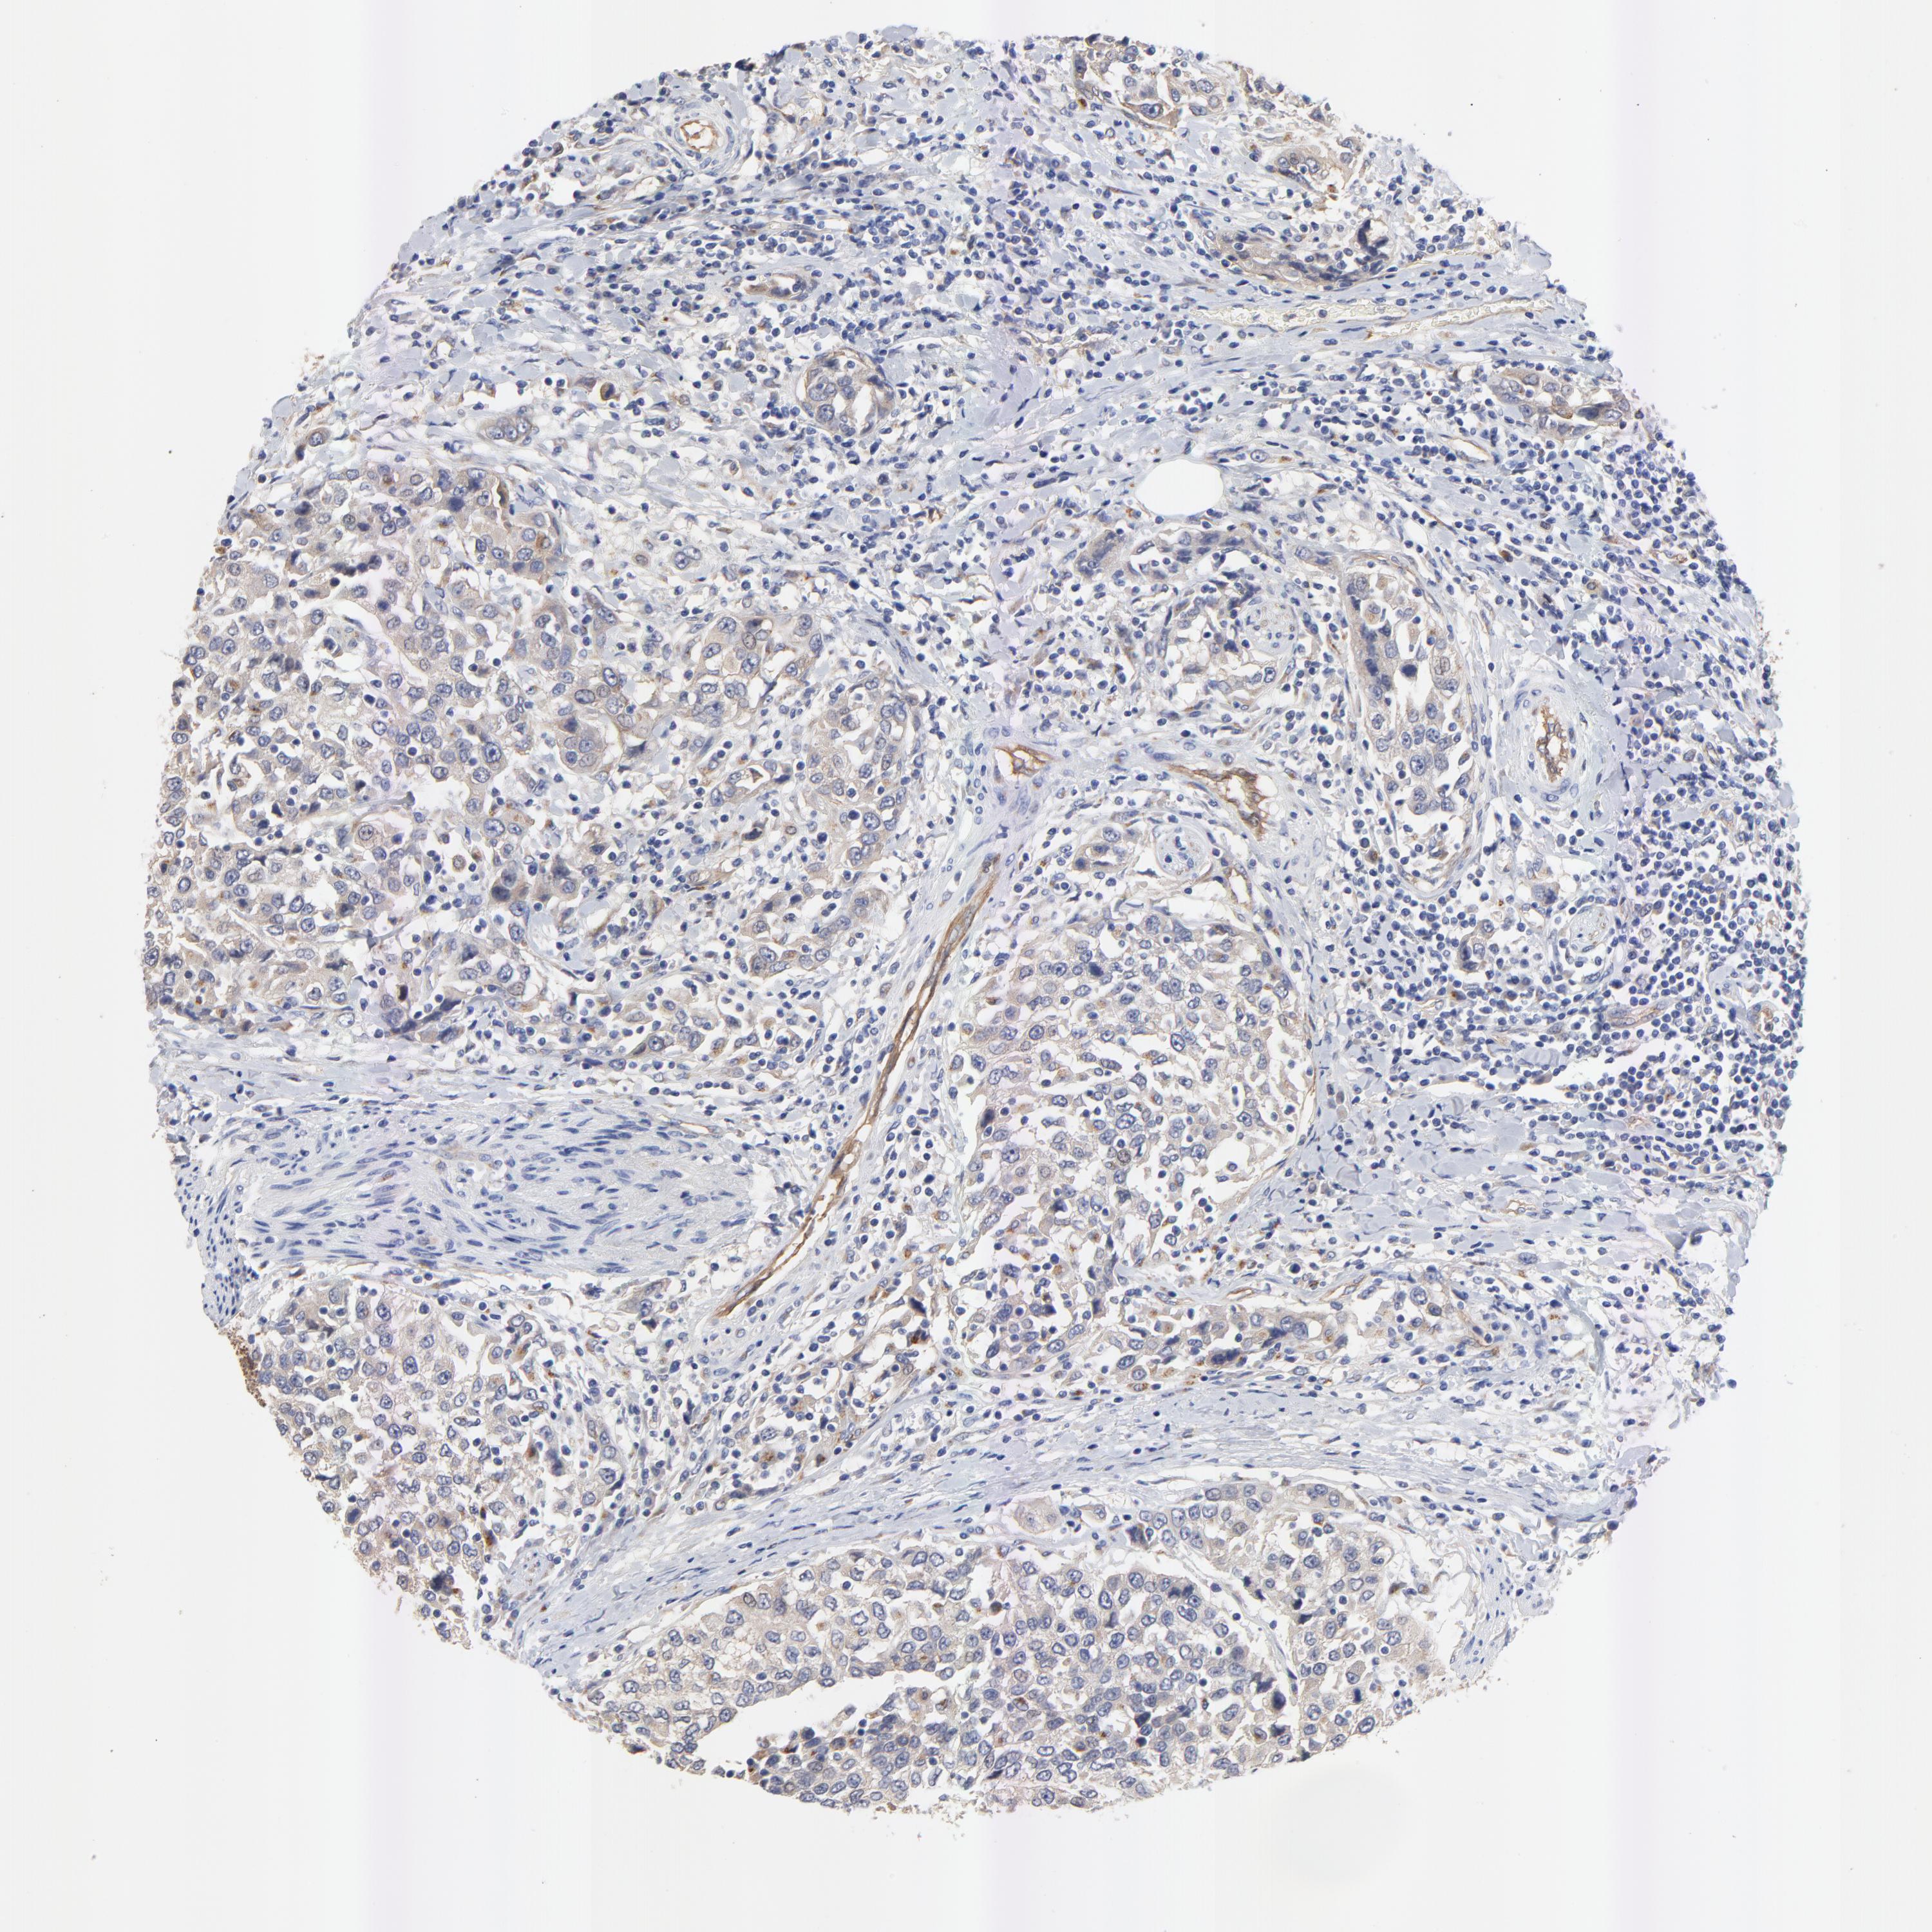

UROTHELIAL CANCER - Protein expressioni

A mouse-over function shows sample information and annotation data. Click on an image to view it in a full screen mode. Samples can be filtered based on level of antibody staining by selecting one or several of the following categories: high, medium, low and not detected. The assay and annotation is described here.

Note that samples used for immunohistochemistry by the Human Protein Atlas do not correspond to samples in the TCGA dataset.

Antibody stainingi

Antibody staining in the annotated cell types in the current human tissue is reported as not detected, low, medium, or high, based on conventional immunohistochemistry profiling in selected tissues. This score is based on the combination of the staining intensity and fraction of stained cells.

Each image is clickable and will lead to virtual microscopy that enables deeper exploration of all samples and also displays staining intensity scores, fraction scores and subcellular localization as well as patient and tissue information for each sample.

Antibody HPA003240

Staining

High

Medium

Low

Not detected

Intensity

Strong

Moderate

Weak

Negative

Quantity

>75%

75%-25%

<25%

None

Location

Nuclear

Cytoplasmic/membranous

Cytoplasmic/membranous,nuclear

Urothelial carcinoma, High grade

Urothelial carcinoma, Low grade